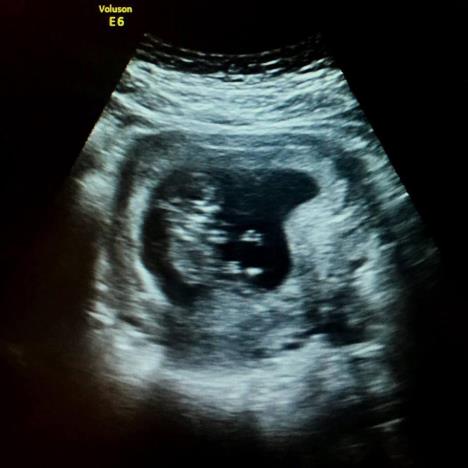

Den Madžeski iz SAD-a objavio je na Fejsbuku da je njegova supruga Lea trudna. Ali, to nije bila obična objava već intimna ispovest o tome što su sve prošli u zadnje tri godine - od uzaludnih pokušaja trudnoće do bolnih spontanih pobačaja. Uz ispovest je stavio i sliku s ultrazvuka i napisao kako čekaju devojčicu. Objavu je sa "sviđa mi se" označilo 46.000 ljudi, a podelili su je gotovo 7000 puta.

Išli smo na test dve nedelje kasnije, i rekli su joj da je trudna. A ti plačeš i plačeš, ogromne suze olakšanja. Nekoliko nedelja kasnije, otišli smo na ultrazvuk. Pa to je punoglavac s ogromnom glavom. Tu je njegov mozak, a tu je i njegovo srce.

Tri skeniranja kasnije, čak smo čuli otkucaje srca, poput kolibrića, i to je lepo. Dok ovo pišem, sutra je naš prvi ginekološki sastanak i tako smo nervozni. Znam dosta ljudi koji su prošli kroz više od nas. Mi smo relativno vrlo srećni. Neki ljudi nikada nisu dočekali trudnoću.

Devojčica je! Imat ćemo devojčicu.